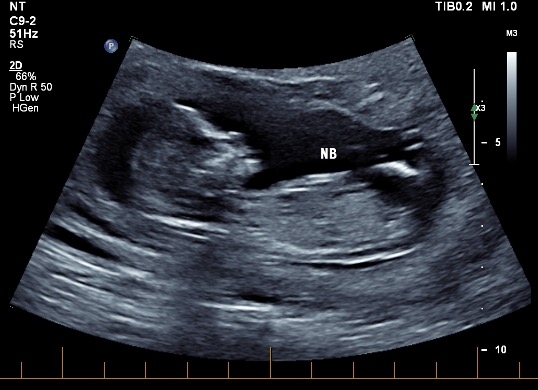

Hi all! I'd love some opinions here, I'm not even sure if there's a nub to see in any of these pictures. These were taken at exactly 13 weeks. I'm now 19 weeks and still have 1 week and 6 days until my anatomy scan (not that I'm counting or anything!) I have three boys and this is my last baby, so I'd love a little girl! Thanks in advance if anyone can help!

Attachment 35247